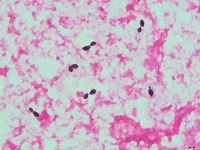

01Acanthosis and spongiosisAcute Tubular NecrosisAcute tubular injuryAdipocytes andFat CellsAlveolar septaAlveolusAlzheimers disease indicating a neurofibrillary tangleAmphibian Simple Columnar EpitheliumAntihippocampal antibodiesAstrocytomaBacterial VaginosisBasaloid CellsBilayer of Cuboidal CellsBinucleated CellsBladder Pain SyndromeBrain Thalamus TissueBullous PemphigoidCOX Reaction